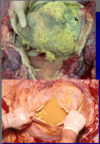

This is a liver. What lesion is shown here?

multifocal hepatic abscesses